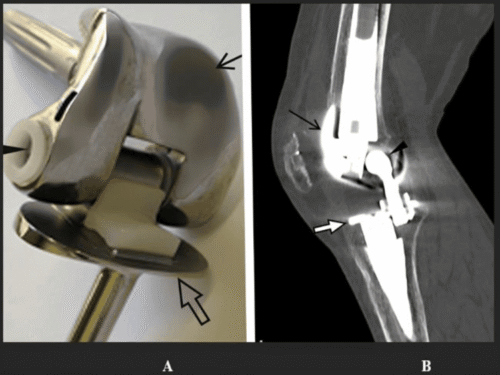

⚠️ ¿Qué son los artefactos en la resonancia asociados a prótesis?

Aunque una prótesis sea compatible, eso no garantiza que no distorsione la imagen.

Los artefactos son un efecto físico del metal sobre el campo magnético.

Como explico a mis pacientes, “aunque una prótesis sea compatible con resonancia magnética, no implica que no cree artefactos en la imagen”.

Un caso típico es el de los brackets o prótesis metálicas cercanas a la zona a estudiar: la resonancia es segura, pero puede no servir para diagnosticar correctamente.

No necesariamente. Aunque la prótesis sea compatible y no suponga un riesgo, puede producir artefactos que alteren la calidad de las imágenes y dificulten la interpretación. En mi experiencia: “aunque un dispositivo o una prótesis sea compatible con resonancia magnética, no implica que no cree artefactos en la imagen”.